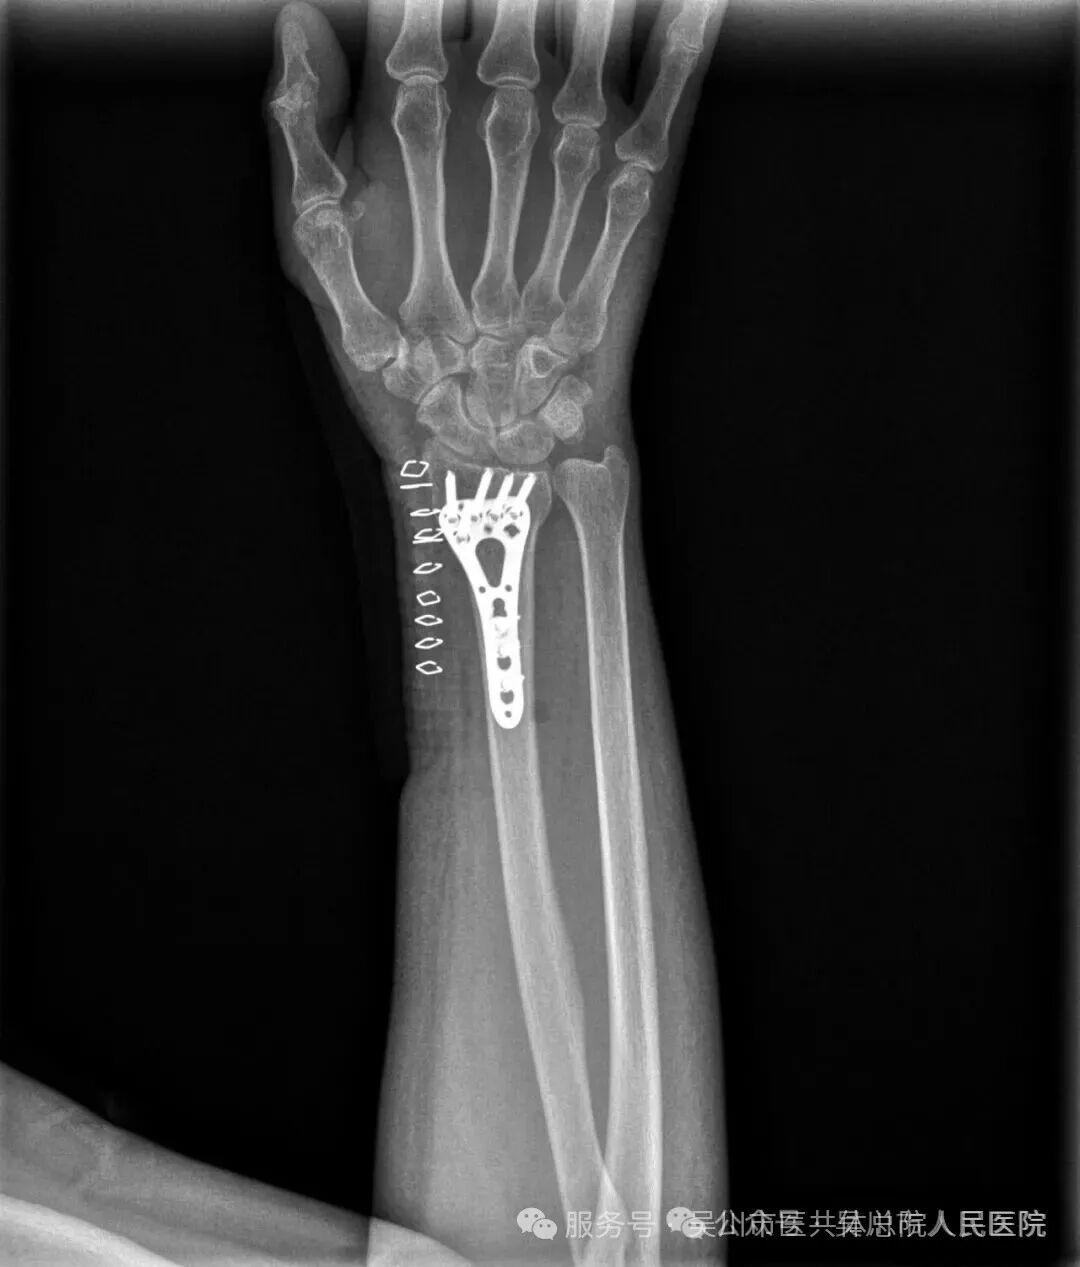

结合潘阿姨的年龄与身体状况,王井旺率手术团队经过缜密讨论,决定采用微创手术治疗方案——依托“百千万工程”专项资助配备的高精度骨折复位设备,在精准定位下实现骨折端解剖复位,再用钛合金钢板进行稳固内固定。该部位骨折若处理不佳,将严重影响手腕功能。面对潘阿姨的病情与忧虑,骨一科团队快速响应,曾文晓副主任医师、欧春云副护士长、王井旺耐心向患者及家属详解病情,舒缓家属焦虑情绪。

为最大限度恢复手腕功能、减少后遗症,经全面术前评估,手术由王井旺主刀。手术当天,无影灯亮起,王井旺手持器械的动作沉稳而精准,眼神锐利如炬,他避开血管与神经密集区域,术中发现潘阿姨骨折碎片存在隐匿性移位,王井旺没有急于操作,而是结合术前影像反复确认复位角度,最终凭借近20年创伤骨科经验,精准调整钢板位置,确保术后关节功能不受影响,这一幕被在场护士记录为“教科书级的手术决策”。整个过程中,护士团队默契配合,精准传递器械,麻醉医生紧盯监护仪上的生命体征,手术室里器械碰撞声与监护仪的滴答声交织成专业的节奏,每一个环节都严丝合缝。

得益于术前精准手术与术后科学护理,潘阿姨的康复进程远超预期。复查结果显示,她的右腕掌屈32°、背伸38°,活动度已接近正常生理范围,日常生活能力基本恢复,不仅能自主穿衣、洗漱,还能重新拿起厨具炒菜做饭。“真的太感谢王医生和护士们了!”潘阿姨的感激之情溢于言表。